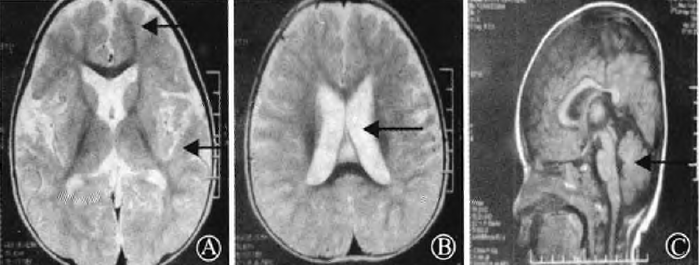

查体:表情欣快,身高正常,头围小,下颌长,心、肺、腹无明显异常,四肢肌力Ⅳ级,肌张力偏低,深浅感觉粗测均无异常,腱反射正常引出,独走时步基宽,动作僵硬,稳定性差。实验室检查:血、尿、便常规,血生化及心电图未见明显异常,脑电图示以右侧后头部为主较多量多棘慢波发放。颅脑MRI示双侧侧脑室扩大,弥漫性脑沟深,脑回细,脑白质偏少,脑萎缩(图)。